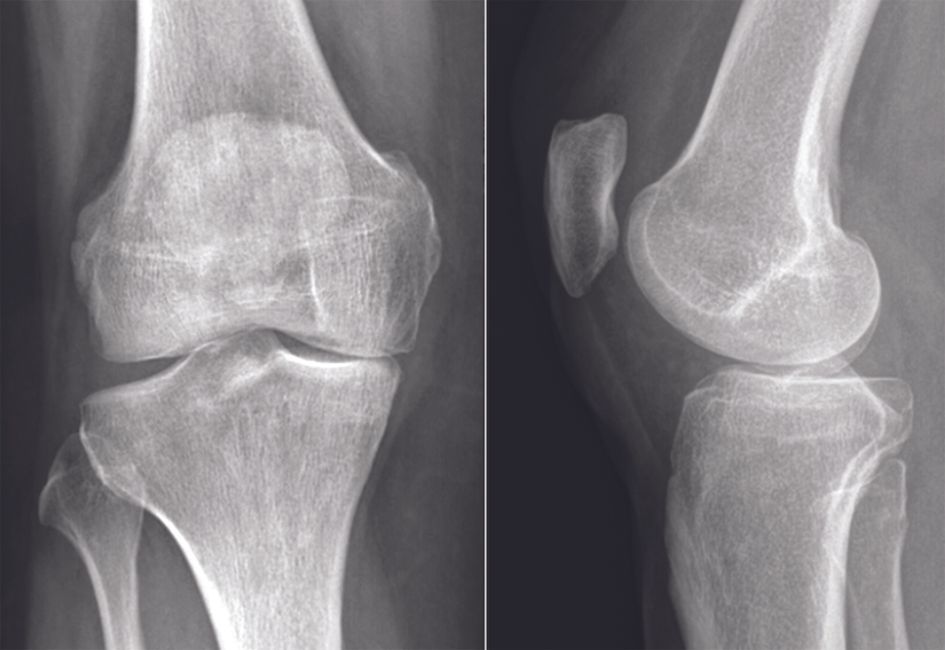

Technique Guide de Coupe, de Correction et de Positionnement d’implant « Patient’s Specific » dans les Ostéotomies Tibiales de Valgisation , Matthieu Ollivier Institut du Mouvement et de l'Appareil locomoteur, Assistance Publique des Hôpitaux de Marseille, Aix-Marseille Université, Marseille, France , Christophe Jacquet Institut du Mouvement et de l'Appareil locomoteur, Assistance Publique des Hôpitaux de Marseille, Aix-Marseille Université, Marseille, France , Jean-Noël Argenson Centre de Chirurgie de l’Arthrose - Hôpital Sainte Marguerite, Université Aix-Marseille II, Marseille, France , Sébastien Parratte Centre de Chirurgie de l’Arthrose, Hôpital Sainte Marguerite, Université Aix-Marseille II, Marseille, France , Xavier Flecher Hôpital Sainte Marguerite, Université Aix-Marseille II, Marseille, France N°275 - Juin/Juillet 2018 ● 7 min de lecture